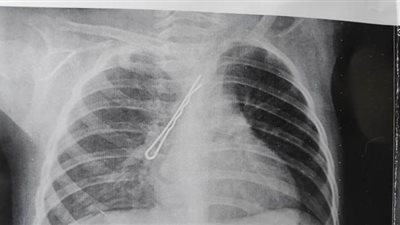

تمكن فريق طبى بقسم جراحه القلب والصدر بالمستشفى الجامعي بسوهاج من استخراج بنسه شعر يبلغ طولها ٣ سم